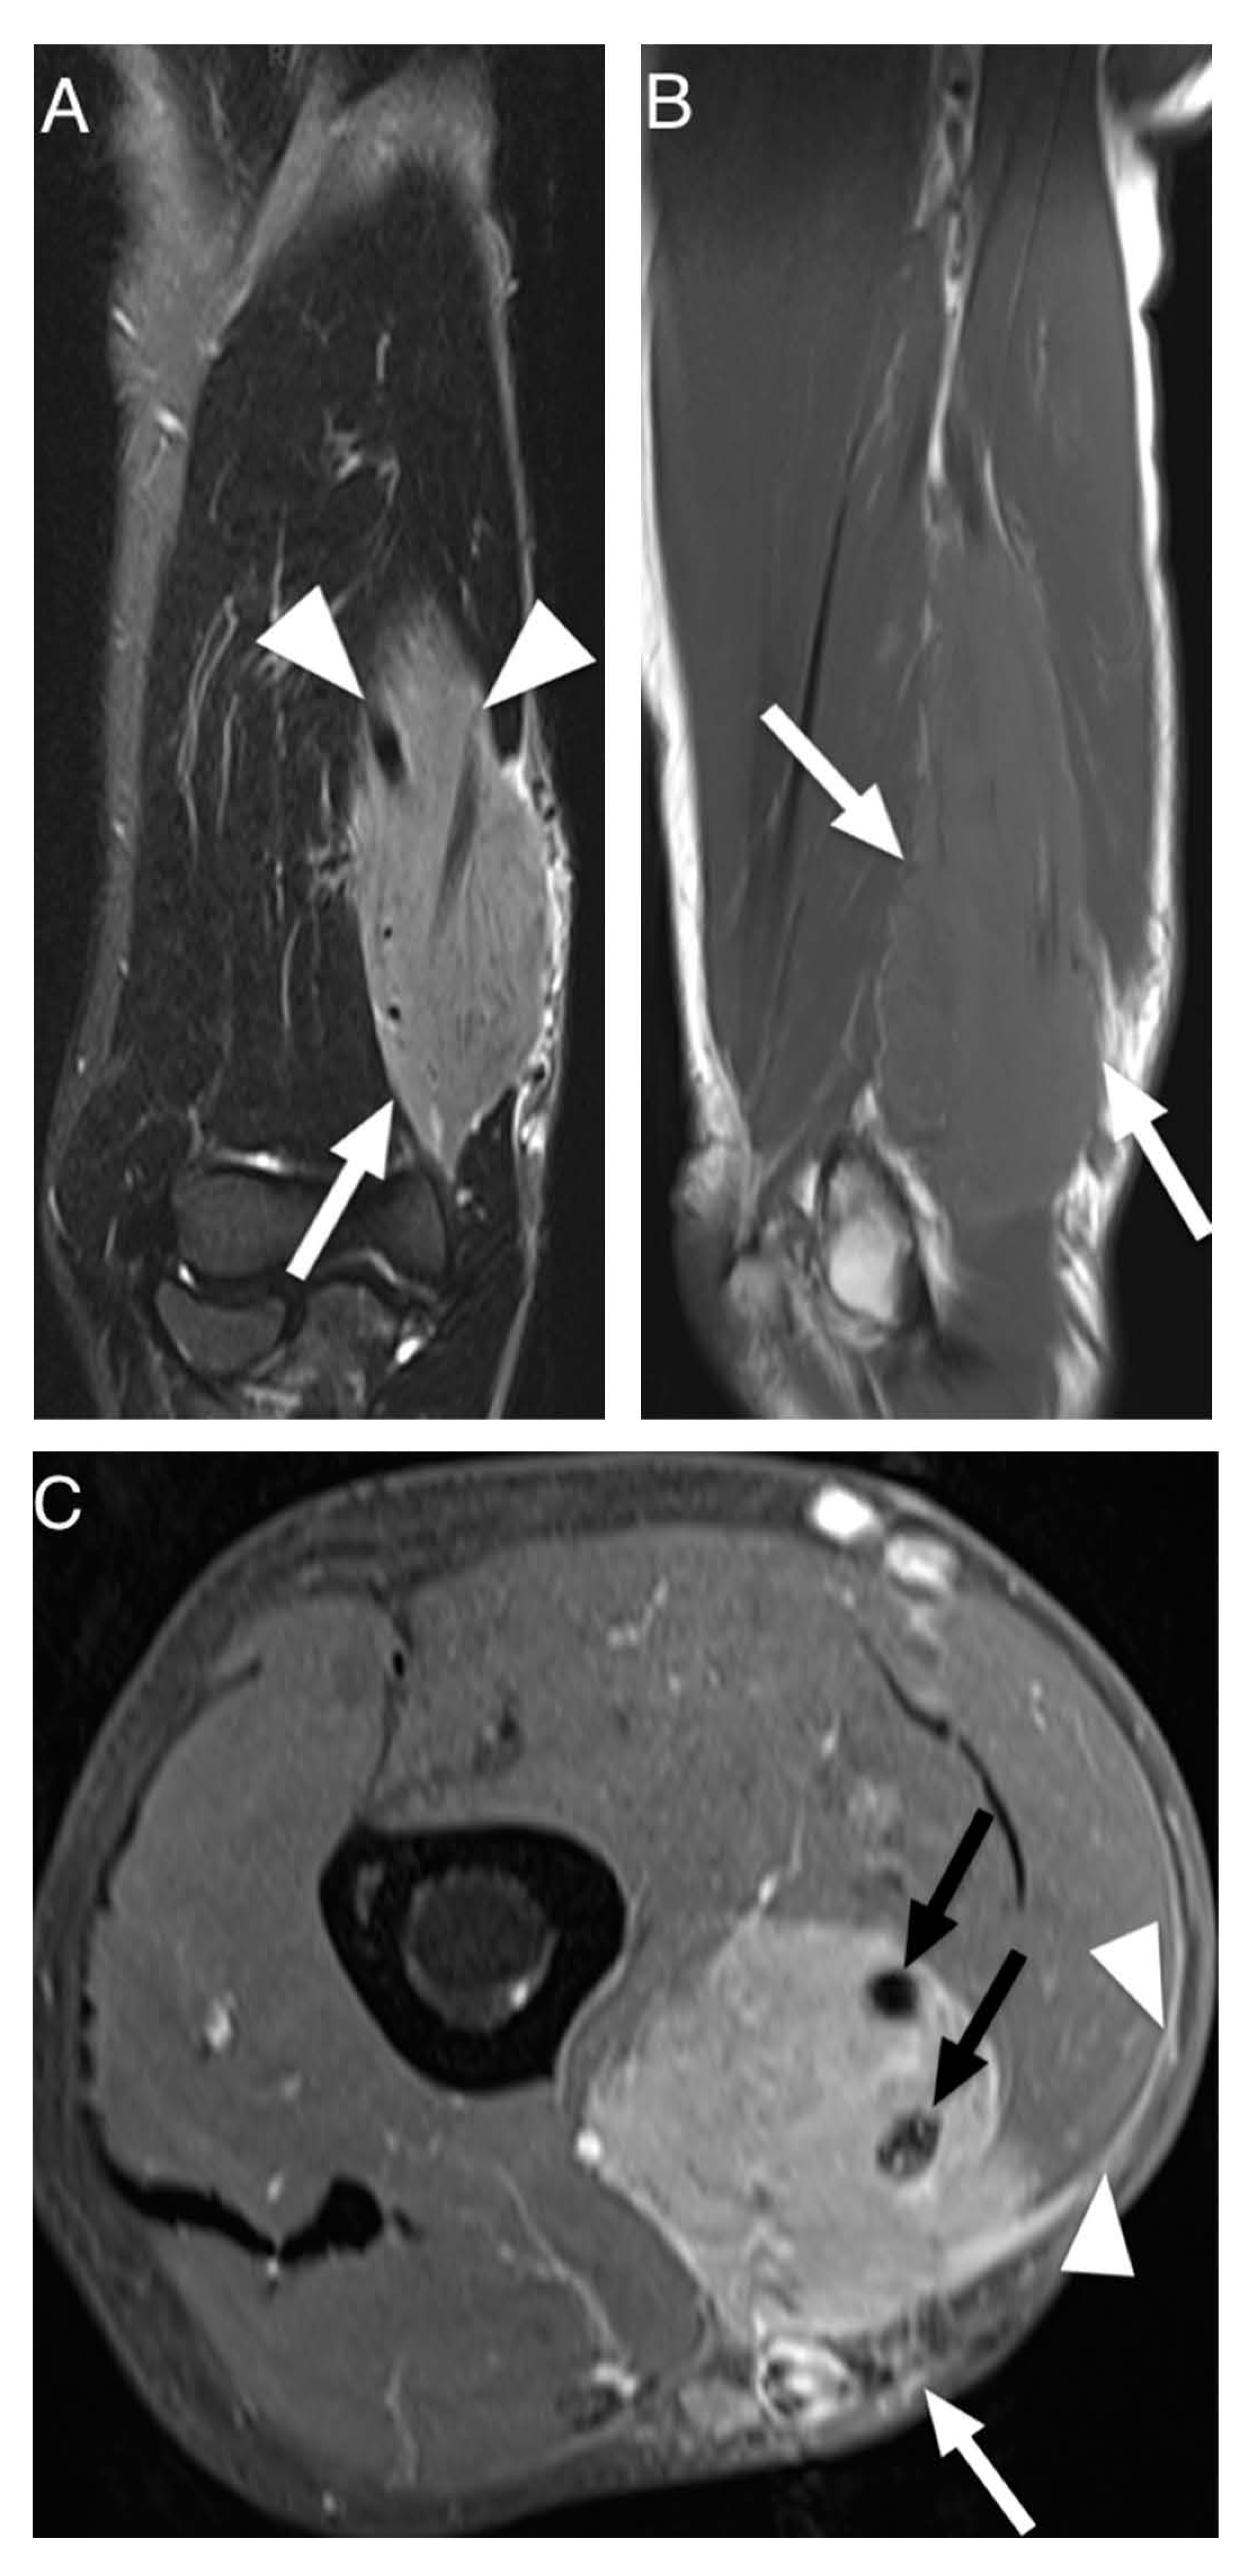

4. Discussion